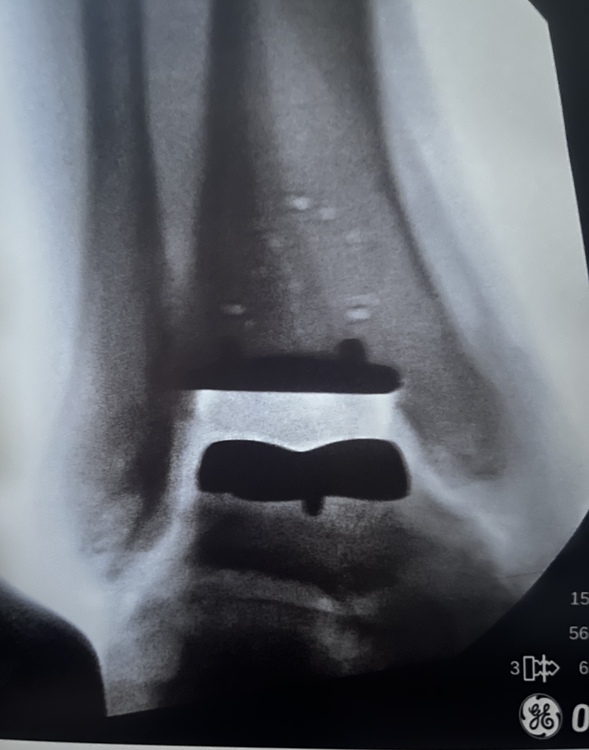

I had my total ankle replacement surgery this morning and I’m back home recovering. I thought I’d share for those interested. Pre op and current view of my right ankle. The climbing shoes provide a reference point for my pre op ankle. |

TK421wrote: Which TAR do you have yourself? Do you have any images to share or you TAR? |